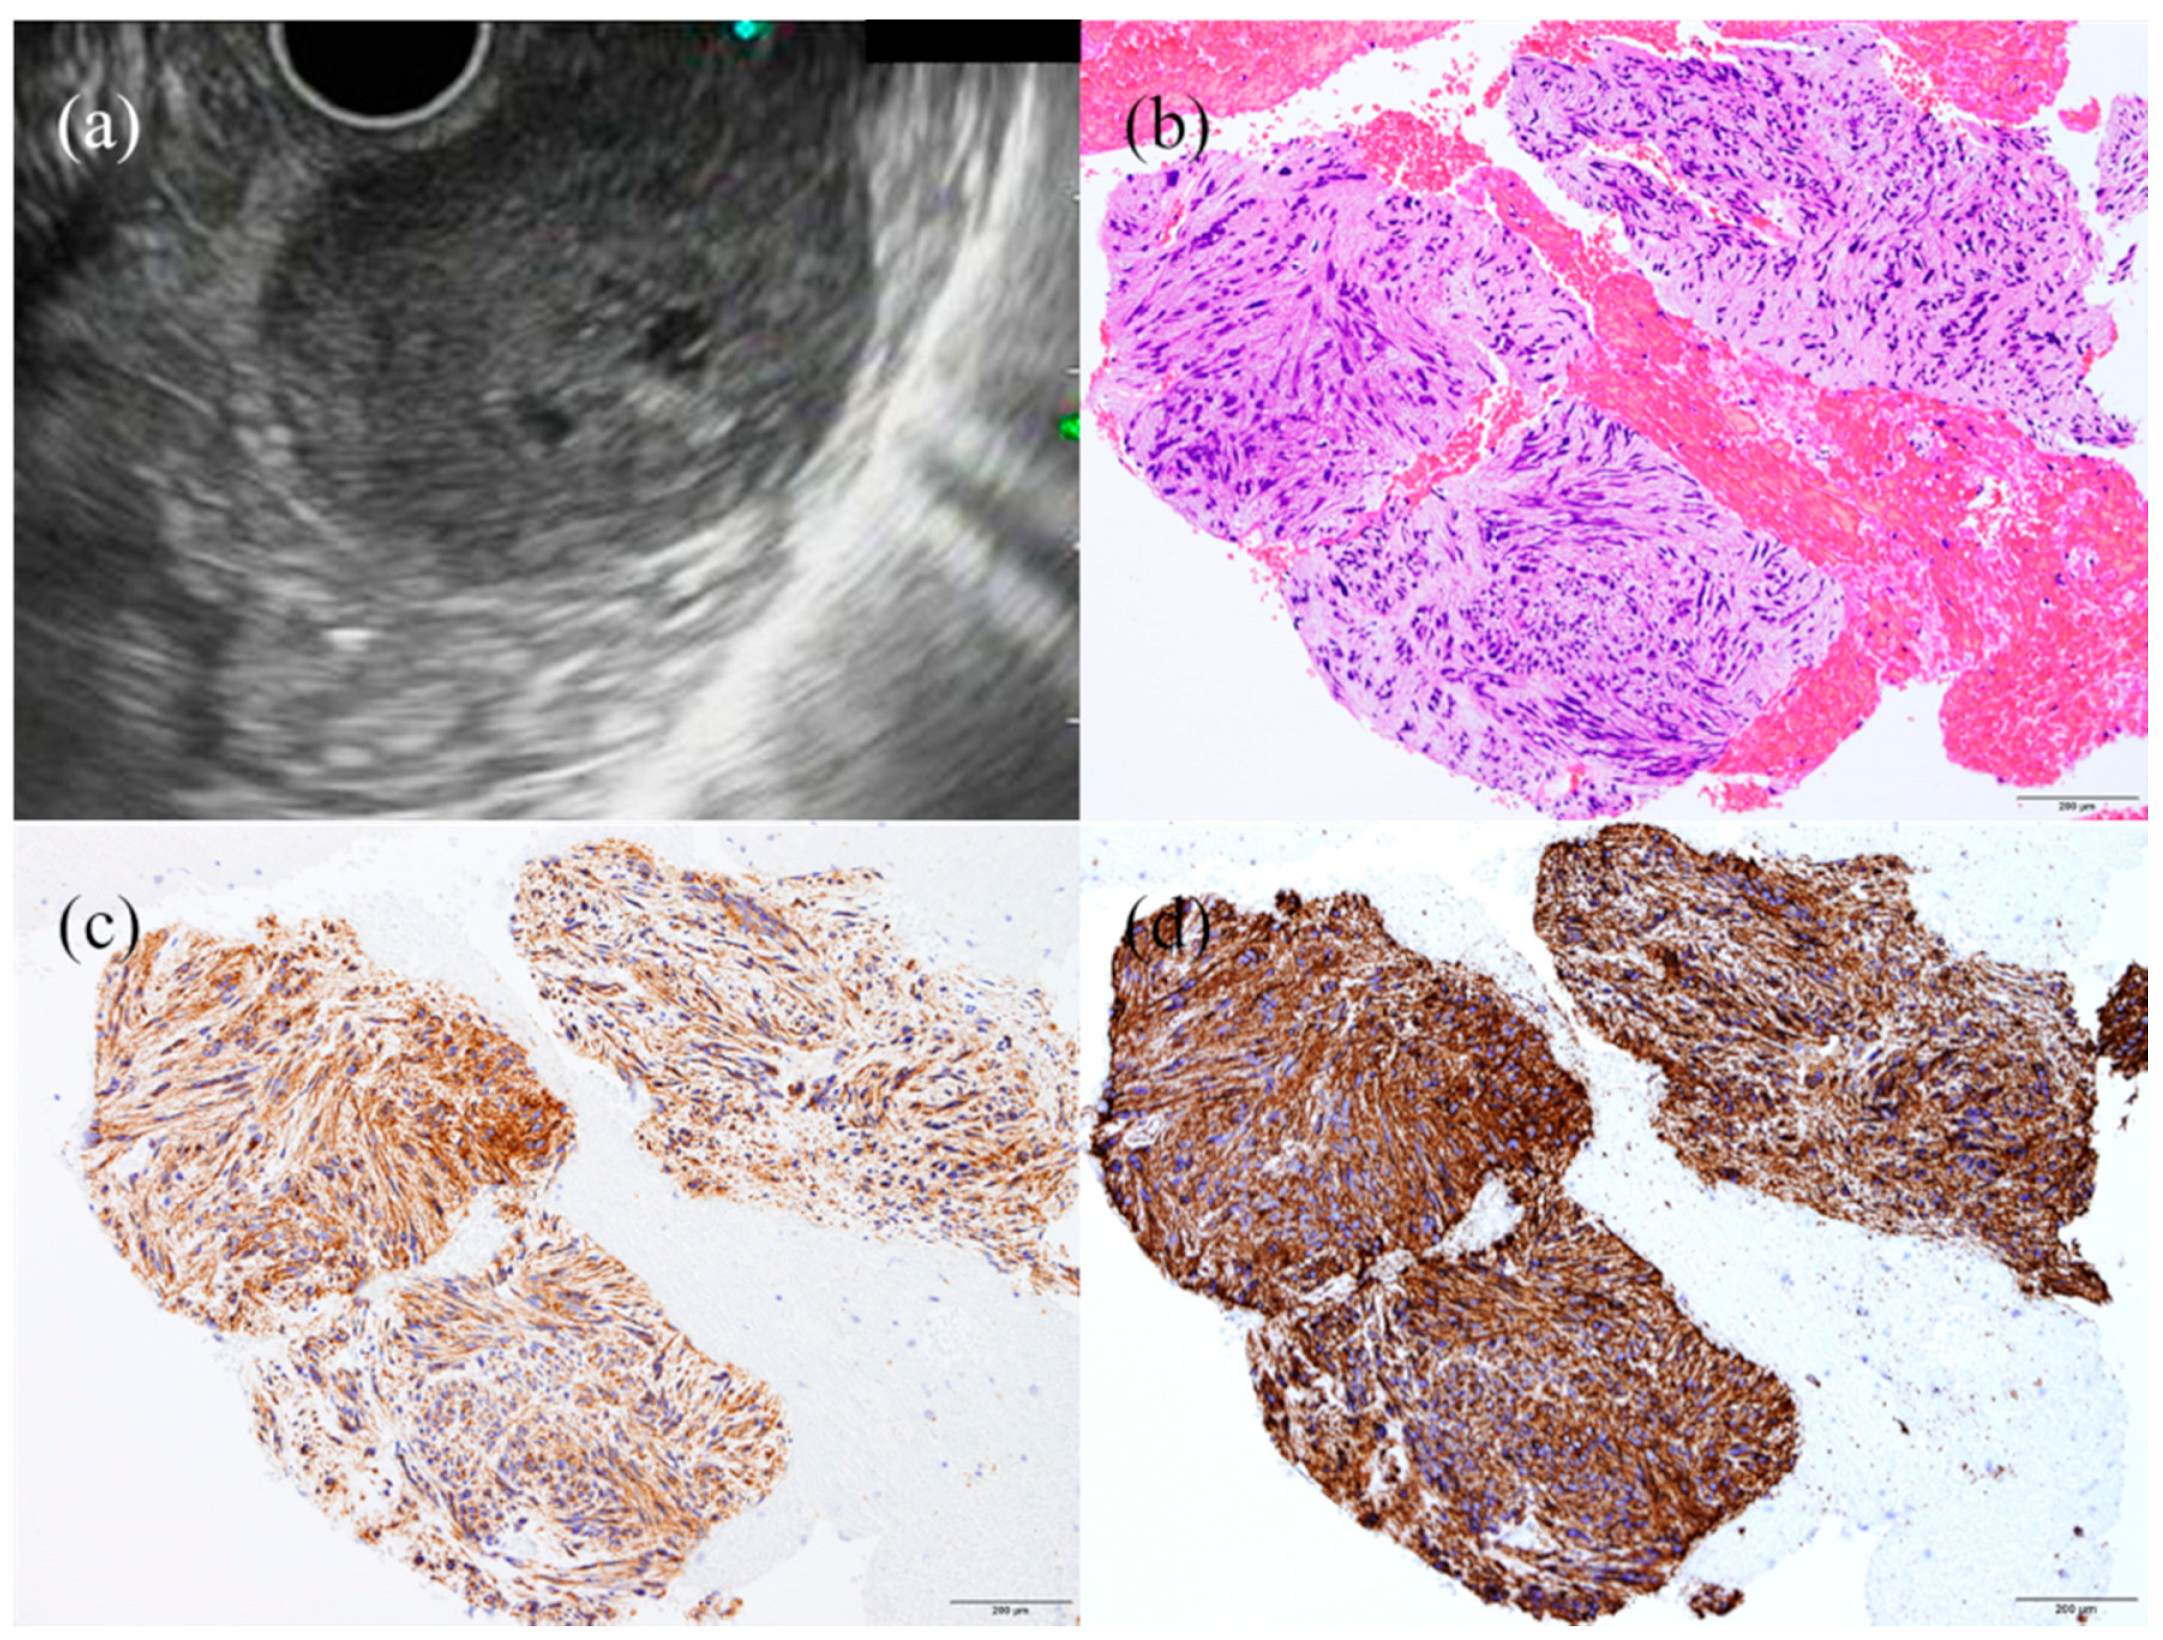

- Fujita, A.; Ryozawa, S.; Kobayashi, M.; Araki, R.; Nagata, K.; Minami, K.; Tanisaka, Y.; Kobatake, T.; Mizuide, M. Diagnostic ability of a 22G Franseen needle in endoscopic ultrasound-guided fine needle aspiration of subepithelial lesions. Mol. Clin. Oncol. 2018, 9, 527–531. [Google Scholar] [CrossRef]

| Leiomyoma | 2nd or 4th | Hypoechoic (iso- or hypoechoic compared to muscle layer), homogeneous, sometimes calcifications | Desmin (+), α-SMA (+) | None (primary leiomyosarcoma: extremely rare) |

| GIST | 4th | Benign features: small (≤2 cm), oval or round, hypoechoic but relatively hyperechoic compared to muscle layer, homogeneous Malignant features: large (>3 cm), irregular margins, heterogeneous echotexture, cystic spaces, hypervascularity, marginal halo, hyperechoic spots/echogenic foci | KIT (+), CD34 (+), desmin (+), S-100 (-), DOG1 (+), or a mutation search of the KIT or PDGFRA gene | 10–30% clinically malignant |